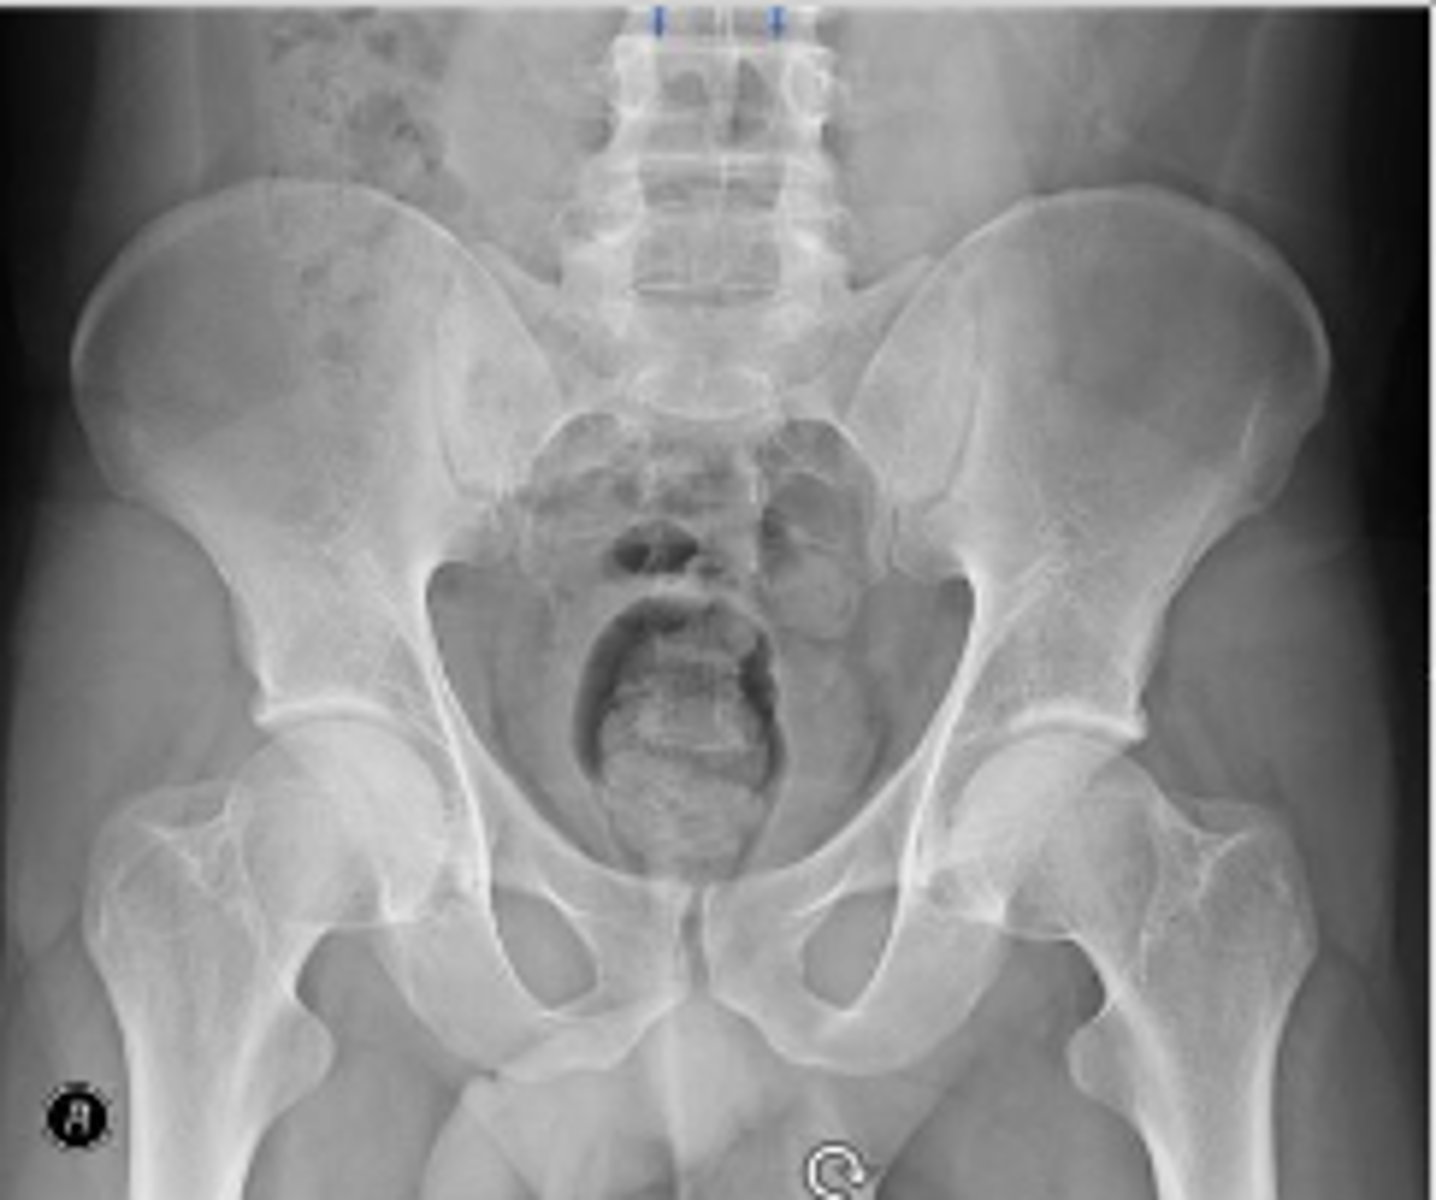

Right AP hip

What is the name of the radiographic view?

Left and right posterior inferior iliac spine

What are the arrows pointing to?

Posterior rim of the left acetabulum

AP pelvis or bilateral hips

Bilateral frog leg view

Phleboliths

Right ischial spine

Posterior rim of the right acetabulum

Anterior rim of the right acetabulum

Right sacroiliac joint space

What joint space is the arrow pointing to?

Lesser trochanter of the right femur

Greater trochanter of the right femur

Right posterior inferior iliac spine

Intertrochanteric line of the right femur

Right ischial tuberosity